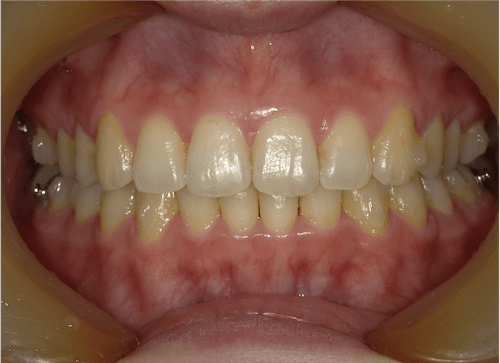

叢生(中等度)

BEFORE

AFTER

担当医コメント

上下の中等度の叢生がある。上顎の大臼歯の遠心移動が出来るスペースがある、補綴が多いのでIPRによってスペースが確保出来るのでインビザラインで治療を行った。

治療の概要

年齢/性別

26歳 女性

主訴

上下の歯並びが気になる。八重歯が気になるでした。

リスク

歯肉退縮が起こる可能性がある。叢生の改善により、ブラックトライアングルが出て来る可能性がある。

費用

85万円(矯正費用)

術前

術中

術後